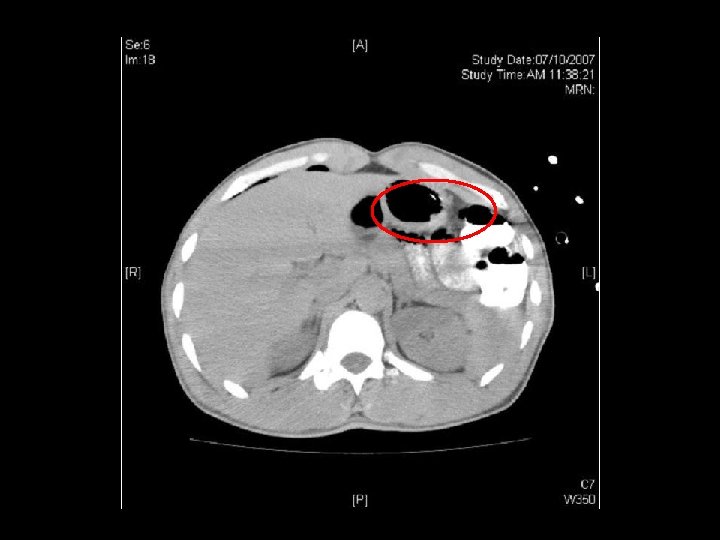

Dx: decompression sickness bilateral chest drain inserted Bilateral myringotomies performed 1 st session of recompression Urgent contrast swallow: no definite leakage in thoracic region

2 nd, 3 rd and 4 th session recompression on D 2, D 3 and D 4 respectively Persistent RUL monoparesis CT brain: hypodensity over L frontaloccipital lobe ? recent infarct MRI brain: acute infarct over L frontoparietal region Dx: deompression illness with pneumothorax, pneumoperitoneum and cerebral air embolism